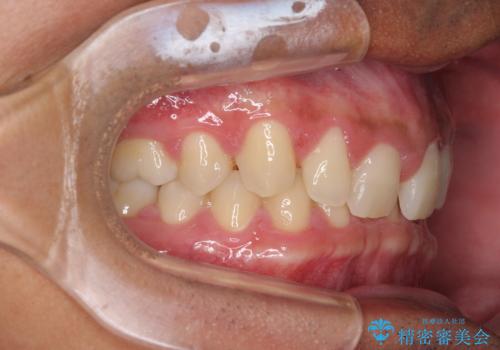

隙間の原因は、埋伏や前後に重なってしまっている上顎小臼歯と、下の前歯が見えなくなるくらいのディープバイトで、それらを改善する必要がありました。

アンカースクリューを用いて下に位置している上顎前歯を持ち上げるとともに、ワイヤー装置によりディープバイトの原因である奥歯の傾斜を改善することで、矯正治療を行っていくこととしました。

また、矯正治療に際し、4本全ての親知らずと、埋もれている右上小臼歯を事前に抜去することとしました。